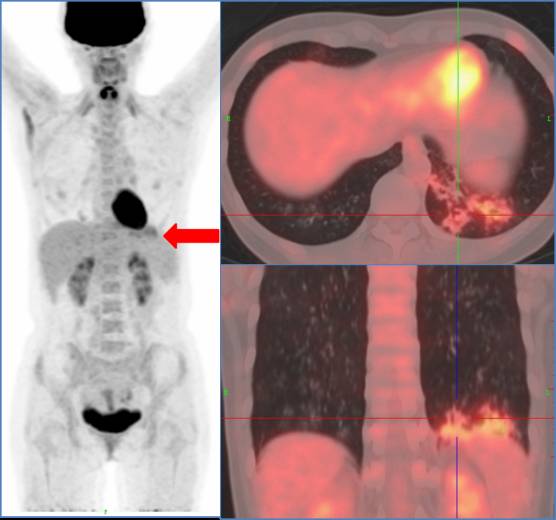

上图为女性,胸片发现左肺结节,PET/CT诊断肺癌。

上图为女性48岁,体检CEA明显升高。PET/CT诊断左肺下叶炎症,抗炎治疗后CEA降低。